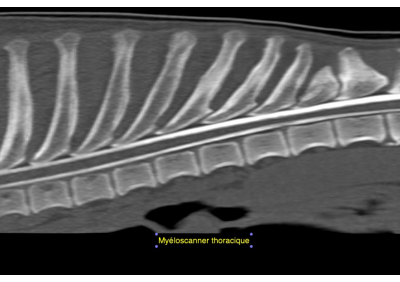

Orthopédie

Caractérisation et visualisation des fractures en 3D qui rendent la planification chirurgicale beaucoup plus précise et efficace, malformations, tendinites, ostéochondrose, fragmentation du processus coronoïde médial, hernie discale, kyste vertébral, diverticule arachnoïdien, spondylodiscite.